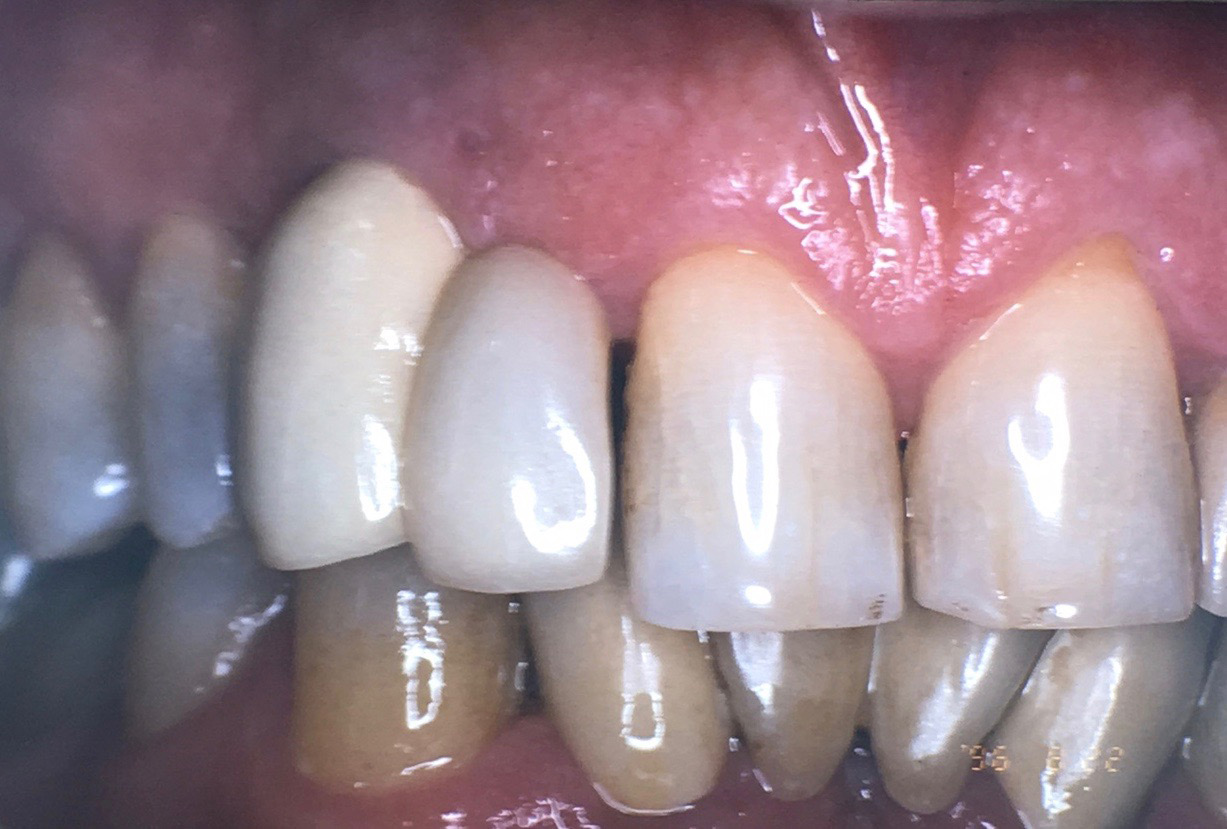

Open proximal contacts between implants and adjacent teeth have been attributed to ongoing craniofacial growth31 and vector forces mesializing tooth position (Figure 16 and Figure 17).32 These changes, particularly in the esthetic zone, can contribute to differences in incisal edge position, gingival margin height, and the facial contour and alignment of the dental arch (Figure 18 and Figure 19).31 Jemt et al30 studied a population of 28 consecutive anterior implant crowns followed for 15 years. During this time, only 8 patients demonstrated no movement of the adjacent teeth; 55% of adjacent teeth displayed palatal tooth movement, predominately in the female population.30 Shifting of teeth can contribute to occlusal changes leading to uneven occlusal load and distribution among the arch.31 Similar to adjacent open contacts between teeth, any open contact can lead to food impaction/accumulation, pocketing, and inflammation of the interdental tissue.

Fig 18. In 1999, teeth Nos. 8 and 9 had the same length with even gingival margins.

Figure 18

Fig 19. In 2016, downward growth of tooth No. 8 could be observed with uneven gingival margins of Nos. 8 and 9.

Figure 19